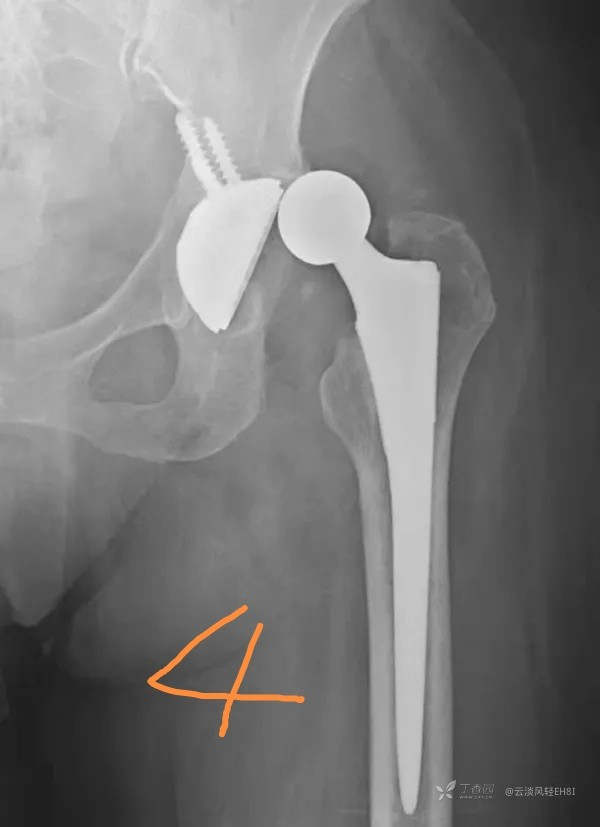

三、脱位(图4)

多发生在术后2~4周,发生率为0.3%~5.4%,通常为假头的前倾角过大以及关节屈曲性痉挛的原因造成。X线片是诊断脱位最佳办法,表现为人工髋关节正常位置关系失常,人工股骨头向外上方移位,位于髋臼假体外。